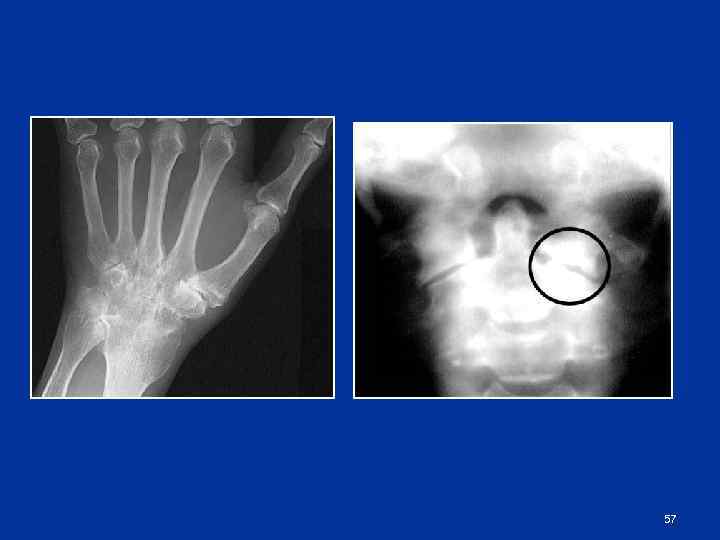

56

57

Костный анкилоз Отсутствие рентгеновской суставной щели n Переход костных балок с одной кости на другую n Отсутствие компактных замыкательных пластин n 58